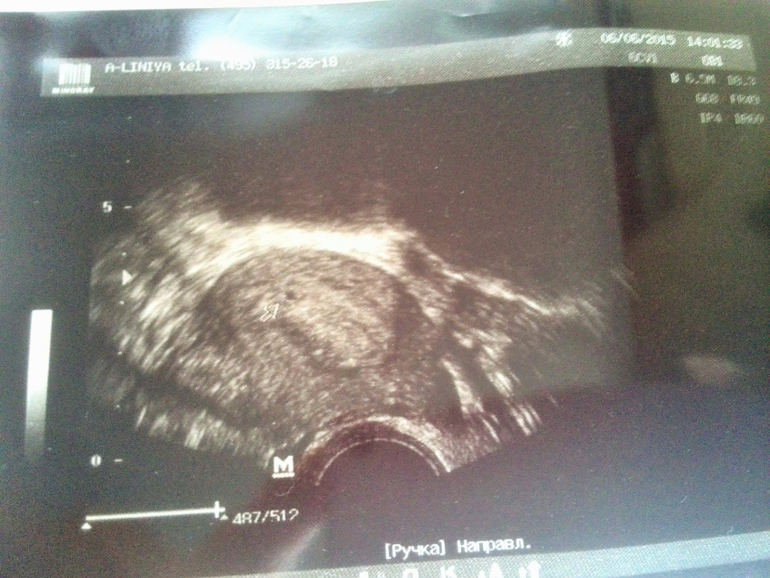

Сходила все-таки на узи

Фолликулометрияуспокоилась более менее))) теперь бы услышать сердцебиение...:)

У меня тоже последние М. 05.05, срок акушерский такой же, но к сожалению на узи не увидели ПЯ, хотя я была 03.06, видимо рановато.. Поздравляю Вас! Держитесь там крепенько и растите!